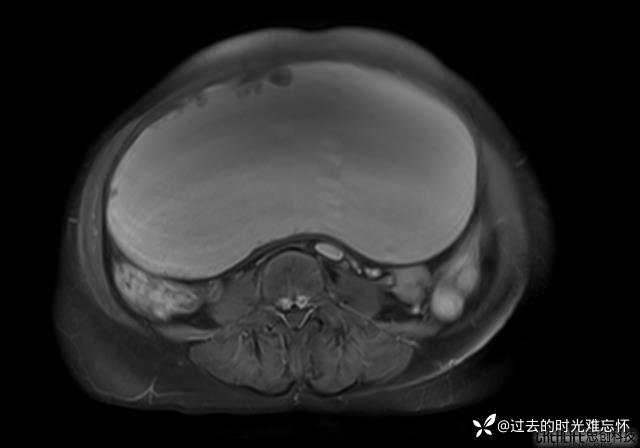

腹大能容5000液;术后腹部好轻松。妙手回春有结果。公布结果。

患者性别:女

患者年龄:65岁

主诉: 发现腹部隆起半年余。无其他明显不适。

浆液性囊腺瘤 (22)